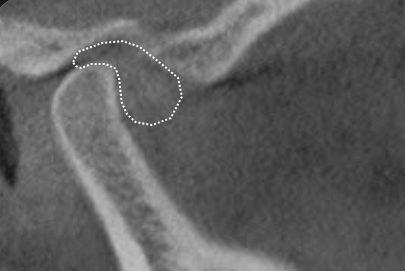

Over 40 million Americans suffer from Myofascial Pain Dysfunction (MPD), a condition that causes headaches and muscular pain. Dr. Klim uses advanced biofunctional diagnostic techniques to decrease painful tension in the head, neck, and shoulder muscles.

Many suffer from Myofascial Pain Dysfunction (MPD) and are not sure of the nature of their condition and how to solve it. You may have heard other terms that describe this condition such as TMJ or TMD. This is short for Temporomandibular Joints. Craniomandibular Dysfunction (CMD) or Temporomandibular Disorder (TMD) are another terms dentist use.